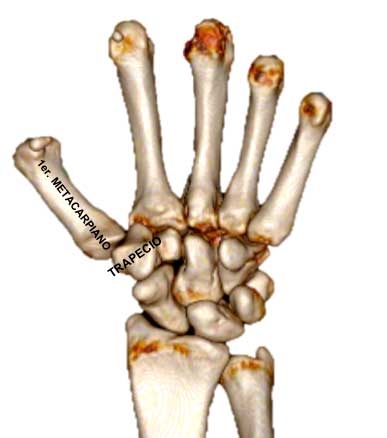

La Rizartrosis, o artrosis de la raíz del pulgar, es la lesión degenerativa más frecuente en la mano debida al desgaste progresivo de la articulación entre el trapecio y el primer metacarpiano.

Radiológicamente, el espacio entre el trapecio y el metacarpiano ha disminuido.

Dependiendo del grado de evolución de la rizartrosis, esta disminución del espacio articular puede evolucionar desde un ligero “pinzamiento” hasta una completa destrucción de la articulación.

- Radiografía: Permite visualizar el grado de desgaste articular, estrechamiento del espacio articular y deformidades óseas.